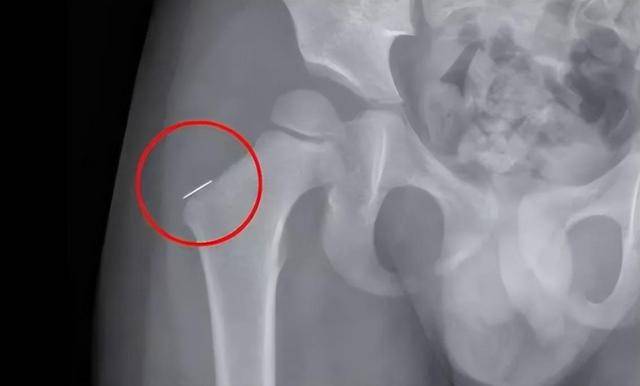

เหตุการณ์เลวร้ายนี้ถูกค้นพบหลังจากที่พี่เลี้ยงออกจากบ้านไปแล้ว เนื่องจากลูกชายร้องไห้เสียงดัง เขาและภรรยาจึงพาไปหาหมอแต่ไม่พบสาเหตุ หลังจากการทดสอบหลายครั้ง แพทย์จึงพบว่าเด็กชายมีชิ้นส่วนโลหะสนิมยาว 3 ซม. จำนวน 2 ชิ้นในร่างกาย ชิ้นหนึ่งในนั้นอยู่ในตำแหน่งที่อันตรายถึงขั้นถูกตรึงไว้ที่กระดูกด้วยซ้ำ หากไม่ระวังจะโดนเส้นประสาทและหลอดเลือดแดง ซึ่งอาจเป็นอันตรายถึงชีวิตได้ เมื่อสามีภรรยาได้ยินดังนั้น พวกเขาก็อดไม่ได้ที่จะตกตะลึง